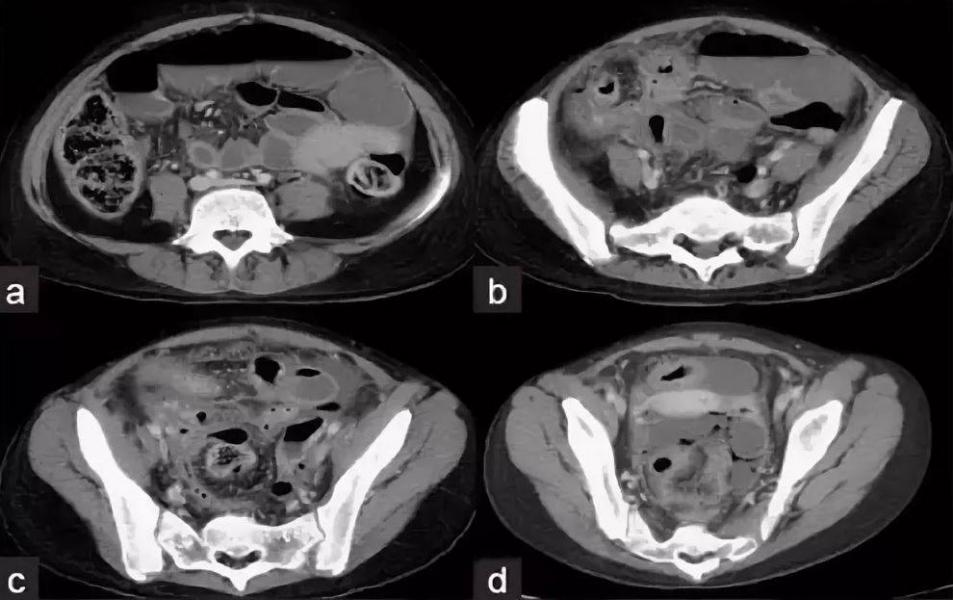

Компьютерная томография органов малого таза нужна для диагностики патологий мочеполовой системы. Также данное исследование необходимо для контроля динамики терапии, оценки состояния мочеполовой системы перед выполнением хирургического вмешательства и после него. Зачастую при томографии необходимо контрастирование, при котором препарат вводится внутривенно. Применяют смесь с содержанием йода, в результате рентгеновские лучи не проникают через контраст. Всевозможные опухоли и болезни сосудов гораздо легче диагностировать с применением контрастного вещества, чем при томографии без использования окрашивания. Контраст является безопасным для здоровья человека, противопоказанием является аллергия к йоду.

Томографию малого таза назначают, когда другие методы диагностики, к примеру узи, не дают четкой картины. Можно выявить следующие состояния: